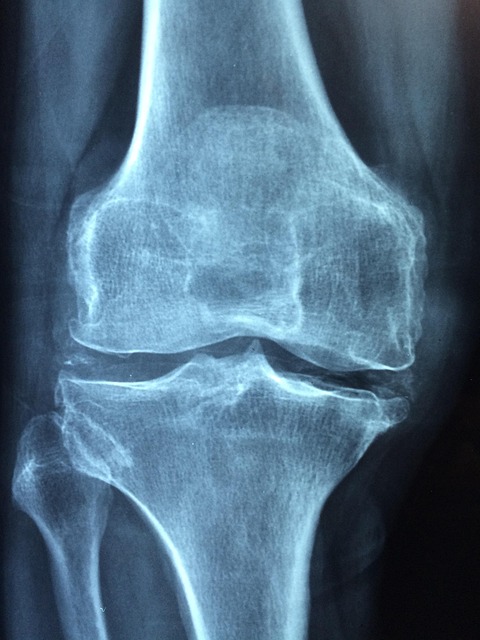

골다공증은 뼈의 강도가 약해져 작은 충격에도 쉽게 골절이 발생하는 질환으로, 특히 50대 이후 여성과 고령층에게 흔하게 나타납니다. 최근에는 약물치료 중에서도 ‘골다공증 주사 치료’가 큰 주목을 받고 있는데, 복약 순응도가 높은 데다 치료 효과가 뛰어나기 때문입니다. 이번 글에서는 가장 많이 처방되는 골다공증 주사 종류와 함께, 각각의 특징·효과·부작용·보험 적용 여부까지 알아보겠습니다. 복용형 약물이 맞지 않거나 더 빠른 치료 효과를 기대하는 환자라면 골다공증 주사 치료가 매우 중요한 선택지가 될 수 있습니다. 이 글을 통해 환자와 보호자 모두가 각 골다공증 주사 종류를 정확히 이해하고, 나에게 맞는 치료 방향을 선택하는 데 도움을 얻으시기 바랍니다.

골다공증 주사 치료는 뼈 밀도를 높이고 골절 위험을 낮추는 데 매우 효과적입니다. 특히 고령층은 약을 꾸준히 복용하는 것에 어려움을 겪는 경우가 많아 주사 치료가 더 적합할 수 있습니다. 월 1회 또는 6개월 1회 등 다양한 투여 방식이 있어 생활 패턴에 맞게 선택할 수 있다는 점도 큰 장점입니다. 정형외과·내분비내과·류마티스내과 등에서 적극적으로 추천하는 이유는, 골다공증 주사가 꾸준히 투여될 경우 골절 위험을 장기적으로 크게 낮추기 때문입니다.